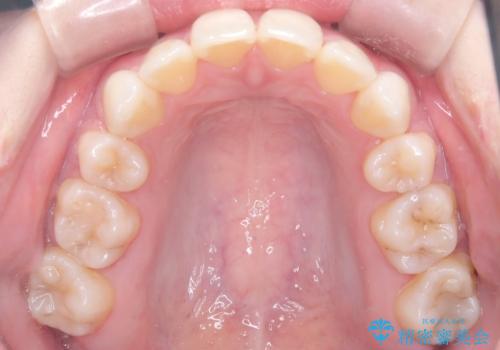

上下4本の抜歯と審美ワイヤー矯正で整った歯並びへ

- 患者様は、歯並びの乱れを整えたいとのことで来院されました。診察の結果、歯列のスペース不足が原因で前歯のガタつきが目立ち、噛み合わせにも影響が出ている状態でした。歯を正しく並べるためにはスペースの確保が必要と判断し、上下の小臼歯4本を抜歯して、審美ワイヤー矯正(白いワイヤーと透明ブラケット)で治療を行う計画を立てました。

まず、抜歯によって歯を動かすためのスペースを確保。その後、審美ワイヤー矯正を用いて、前歯のガタつきを整えながら、噛み合わせの調整も行いました。審美装置を使用することで、矯正中も目立ちにくく、自然な仕上がりを目指して治療を進めました。治療の結果、歯並びがきれいに整い、口元のバランスも改善しました。患者様からは「歯並びがきれいになり、自信を持って笑えるようになった」と喜びの声をいただきました。